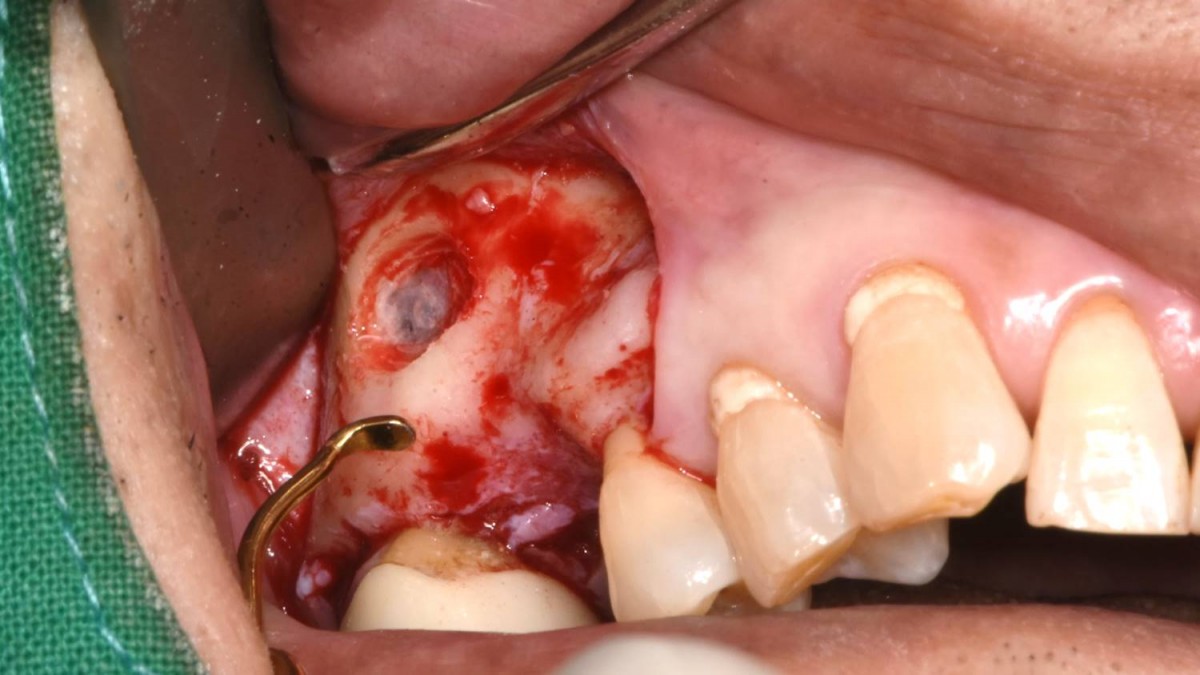

Maxillary Sinus Graft, 2 Implants, Crown Contouring

<GCaks> A 56-year-old male patient had pain-inducing caries, and perio-involved tooth mobility resulted in a tooth fracture at 1st molar. And it was removed months ago. He was a heavy smoker and showed poor oral hygiene.